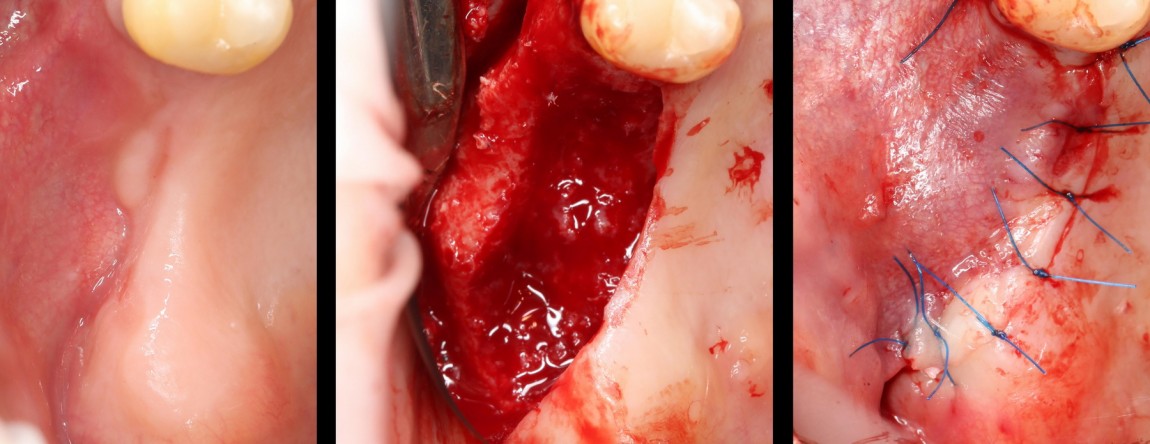

Попытки «утопить» его под слизистую оболочку успеха не имели, мы вынуждены убрать блок полностью. В итоге, мы не достигли нужного результата операции, ее придется повторить. И повторять ее в условиях существующего дефицита слизистой оболочки — это как дважды наступить на одни и те же грабли: вероятнее всего, мы опять пролетим. Поэтому новый этап лечения (точнее, перелечивания) мы начнем с пластики слизистой оболочки. Делается это очень просто — пересадкой кератинизированной десны с нёба:

Фактически, пересаженный слизистотканный лоскут представляет собой заплатку, которой восстанавливается необходимый объем прикрепленной слизистой оболочки. Он просто пришивается там, где десны не хватает:

картинка через день:

и через месяц:

Вот теперь дефицит десны устранен, мы можем приступать к остеопластике. Причем, делаем это несколько иным, нежели изначально планировалось, методом, одновременно с установкой имплантов:

На этот раз рана ушивается вообще без каких-либо проблем. И мы получаем ожидаемый результат имплантологического лечения: